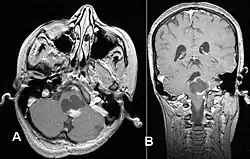

Este tumor se presenta generalmente como una lesión circunscrita y bien delimitada, de crecimiento lento y puede ser sólido o quístico.[2] Suelen apreciarse con facilidad en las imágenes de TC y RM. Los quistes pueden ser monoloculares o multiloculares, con el nódulo tumoral encapsulado en el interior. El astrocitoma pilocítico generalmente aparece a nivel del cerebelo, tronco cerebral, región hipotalámica, nervios y quiasma óptico, y en general en cualquier área donde haya presencia de astrocitos, incluyendo los hemisferios cerebrales y la médula espinal. La localización más frecuente es el cerebelo.[3]

La RM ofrece una mayor sensibilidad en comparación con la TC, si bien no siempre es fácilmente accesible y presenta contraindicaciones, por ejemplo, no se puede utilizar en pacientes con marcapasos, prótesis incompatibles con el campo magnético, clips metálicos, etc. En las imágenes de TC y RM el astrocitoma pilocítico aparece como un tumor con márgenes bien definidos, redondeado, sólido o asociado a macro o microquistes. El 10 % presenta calcificación.[3] La captación de contraste es prácticamente homogénea y muy intensa. Este hallazgo es indicativo de una fuerte vascularización del tumor, aunque en este caso no se considera indicativa de malignidad. En fosa posterior, el diagnóstico diferencial se hace con el meduloblastoma, el ependimoma y el hemangioblastoma, y en la región quiasmática con el craneofaringioma.[9]